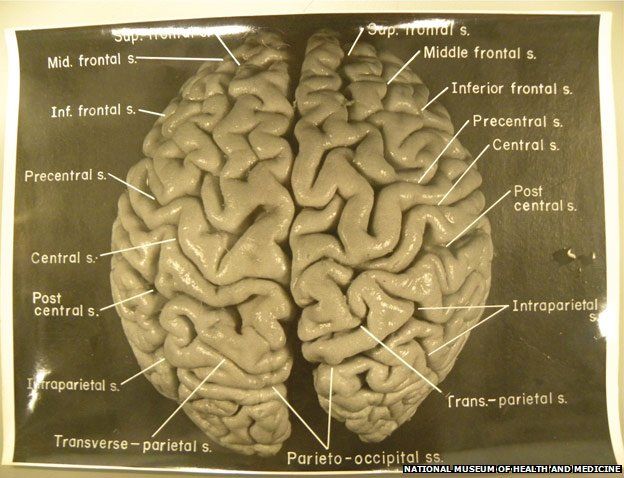

Https www alamy com a specimen of nobel physicist albert einsteins brain is seen in a glass slide at an exhibition at the wellcome collection in london march 27 2012 weve pickled it dessicated it drilled it mummified it chopped it and sliced it over centuries yet as the most complex entity in the known universe the human brain remains a mysterious fascination with samples of albert einsteins preserved brain on slides and specimens from other famous and infamous heads such as the english mathematician charles babbage and notorious mass murderer william burke an exhibition opening in london this week image377121679 html (Dateityp jpg)

Einsteins Brain High Resolution Stock Photography And Images Alamy